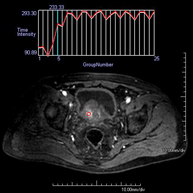

Prueba diagnóstica no invasiva que consiste en la obtención de imágenes de alta definición anatómica de la pelvis mediante el empleo de un campo electromagnético y ondas de radio (con un emisor y un receptor). No utiliza radiación ionizante. Se realiza para estudiar patologías del útero, del ovario, de las trompas y la vagina, ya sean de origen tumoral, inflamatorio o vasculares. Además permite valorar les estructuras adyacentes localizadas en la pelvis, identificando sus alteraciones. A veces requiere el uso de contraste intravenoso (Gadolinio) para caracterizar las lesiones. - RM Pelvis masculina